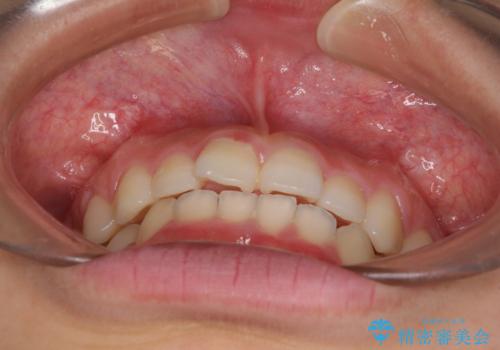

前歯のデコボコと突出感 インビザラインによる矯正治療

- 上下前歯のデコボコと、上顎前歯の突出感を気にして来院された患者様です。

インビザラインによる上下歯列の側方拡大と後方移動、IPR(歯と歯の間を削る)にるスペースの獲得により歯列を整えることとしました。

毎日22時間以上しっかりとマウスピースを装着していただいたので、スムーズに治療が進みました。歯と歯の間を削ることでうまくスペースコントロールでき、1年強で終えることができました。